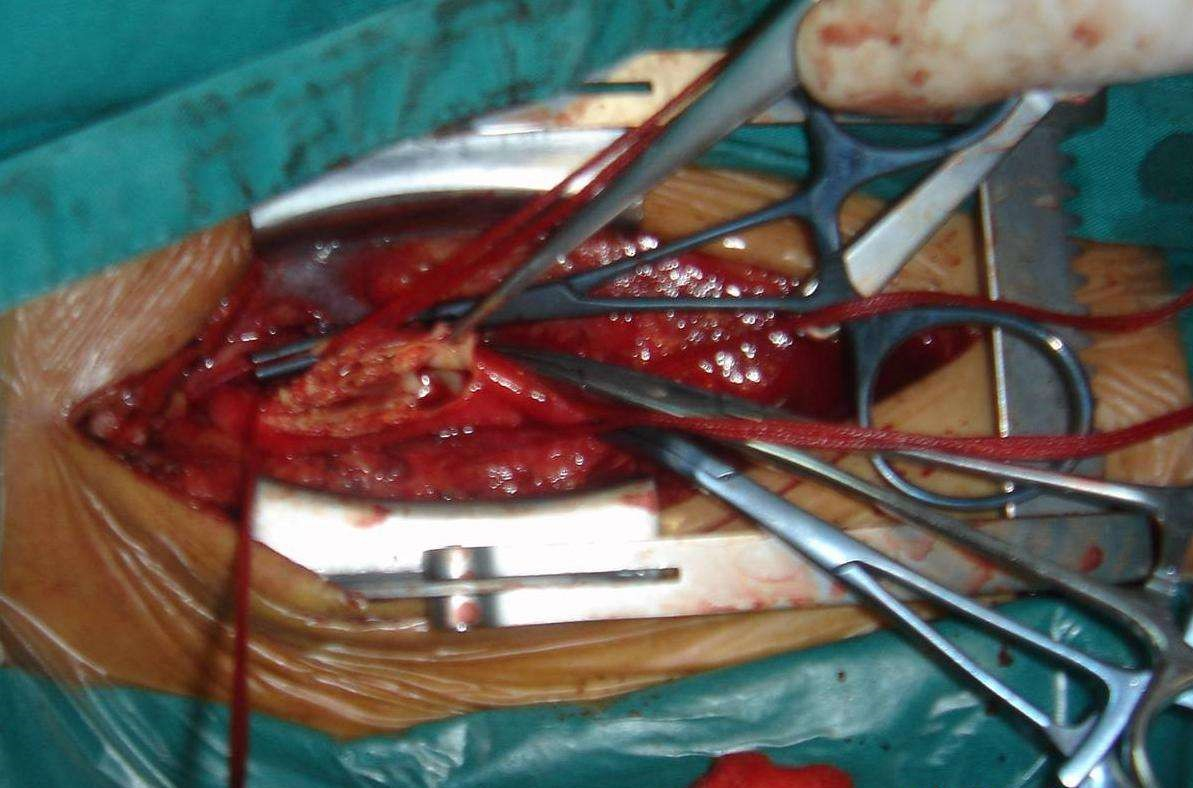

治療腦梗塞手術

治療急性期缺氧性腦梗塞

小腦腦梗塞手術

手術治療腦梗塞的

手術治療腦梗塞

手術治療中的腦梗塞